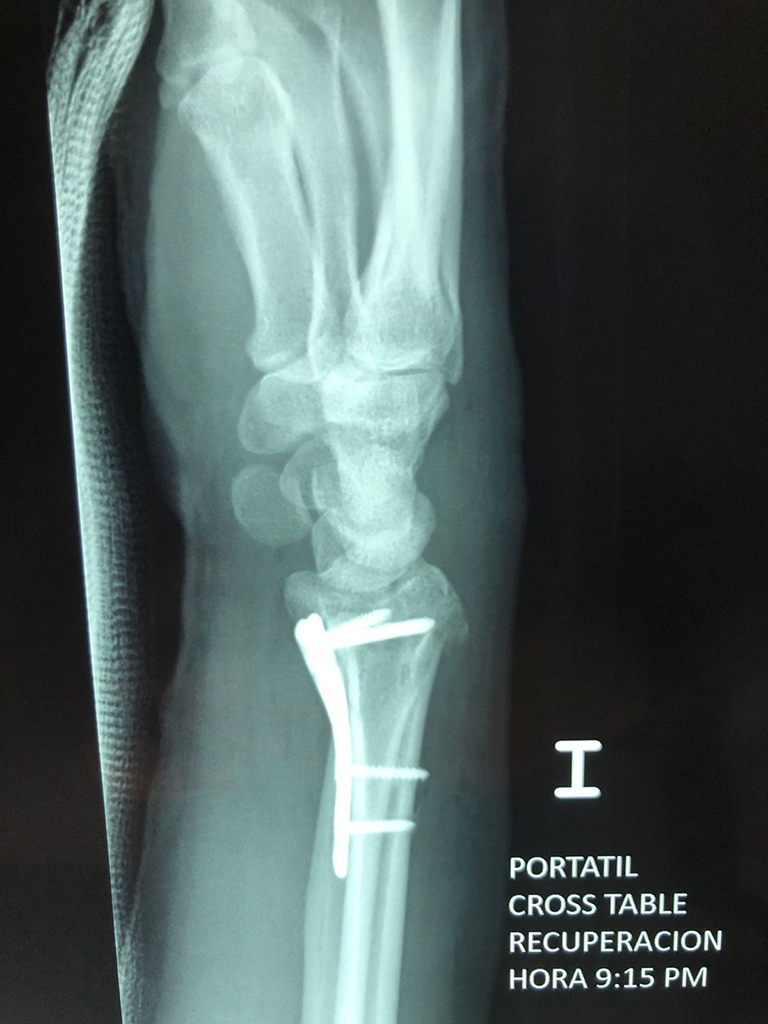

Cirugía de Fémur - Cirugías de Muñecas y Manos

Los procedimientos más comunes en cirugía de la mano son aquellos destinados a reparar traumatismos, incluyendo lesiones de tendones, nervios, vasos sanguíneos, y articulaciones; huesos fracturados; y quemaduras, cortes, y otros daños de la piel.